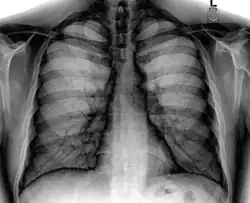

A chest X-ray showing a very prominent wedge-shape area of airspace consolidation in the right lung characteristic of acute bacterial lobar pneumonia.

Consolidation